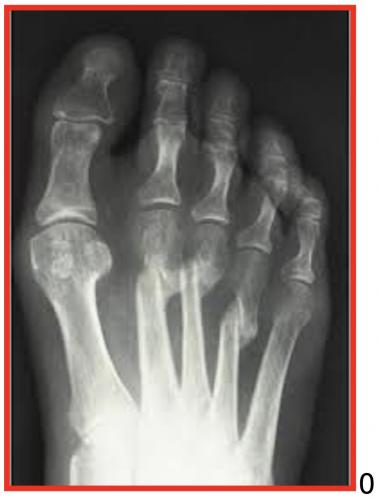

HALLUX VALGUS

Il s’agit d’une déformation qui crée une saillie osseuse sur la partie médiale de l’hallux, à l’origine de phénomènes douloureux et d’une gêne au chaussage. Il s’agit de la déformation la plus fréquente de l’hallux. Elle touche préférentiellement les femmes, parfois dès le plus jeune âge. On ne connaît pas réellement les causes de cette déformation mais l’origine congénitale semble la plus vraisemblable

DIAGNOSTIC :

Saillie douloureuse de la face interne de l’articulation métatarso-phalangienne déformation, bursite, douleur

Radiographie des pieds face et profil en charge +++ avant consultation d’un spécialiste,

Étude de l’architecture global du pied, de l’état articulaire à la recherche d’une arthrose, fracture de contrainte, et mesure des angles.